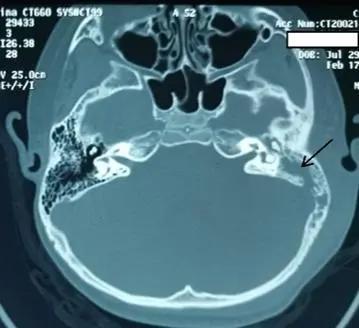

拿出CT一看,很严重!只见左侧中耳和乳突内软组织填充,乳突气房已融合成大腔,外侧软组织肿胀。同侧颅后窝乙状窦表面骨质可疑缺损。这是典型的急性中耳炎的颅外并发症——耳后骨膜下脓肿。